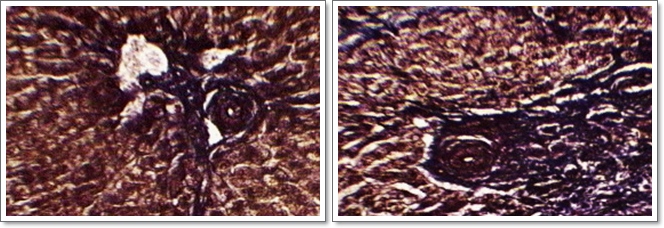

Cerebel:

Està situat a la part darrera del cervell, i és l'òrgan encarregat del control precís dels moviments voluntaris, és a dir, si el cervell decideix fer qualque moviment, dóna l'ordre i es desenté; el càlcul de la quantitat precisa de tensió en cada múscul i l'elecció dels músculs que han d'intervenir són responsabilitat del cerebel.

Cervell:

És el centre més important del sistema nerviós. Controla el funcioname de la resta de centres nerviosos i de vísceres del cos, i és el centre de la sensibilitat general i de les facultats intelúlectuals. De forma directa o indirecta controla i regula les anomenades "constants vitals", és a dir, manté constants els nivells de gran quantitat de paràmetres, com la pressió sanguínia, la temperatura del cos, la composició de la sang, etc. A l'igual que la resta del sistema nerviós, està constitu‹t per neurones, agrupades de forma que els cossos celúlulars queden vers la part exterior (substància grisa), i les connexions a la part interior (substància blanca). Per donar una idea de la seva complexitat, basta dir que el cervell humà conté 10 000 milions de neurones interconnectades i coordinades.